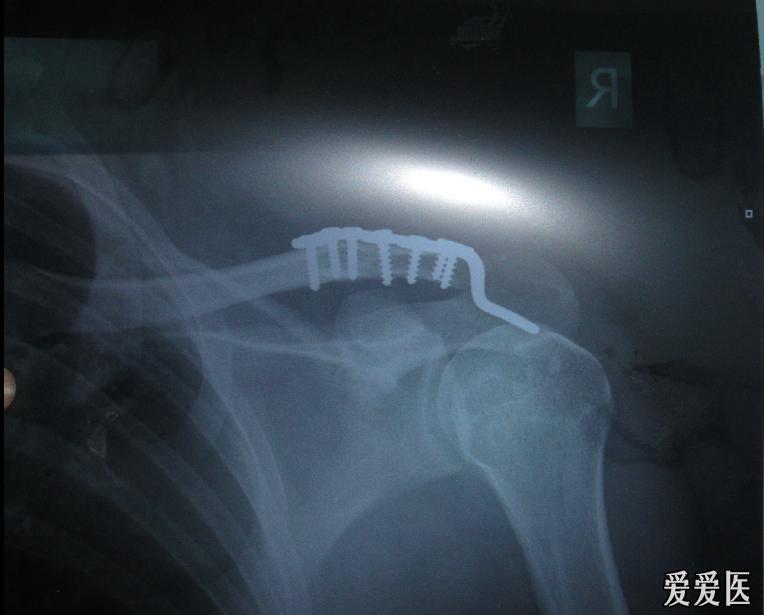

右肩锁关节脱位手术切开复位锁骨钩钢板内固定术求各位看看这次有图

锁骨骨折术后发现肩锁关节脱位(已经更新术后了)